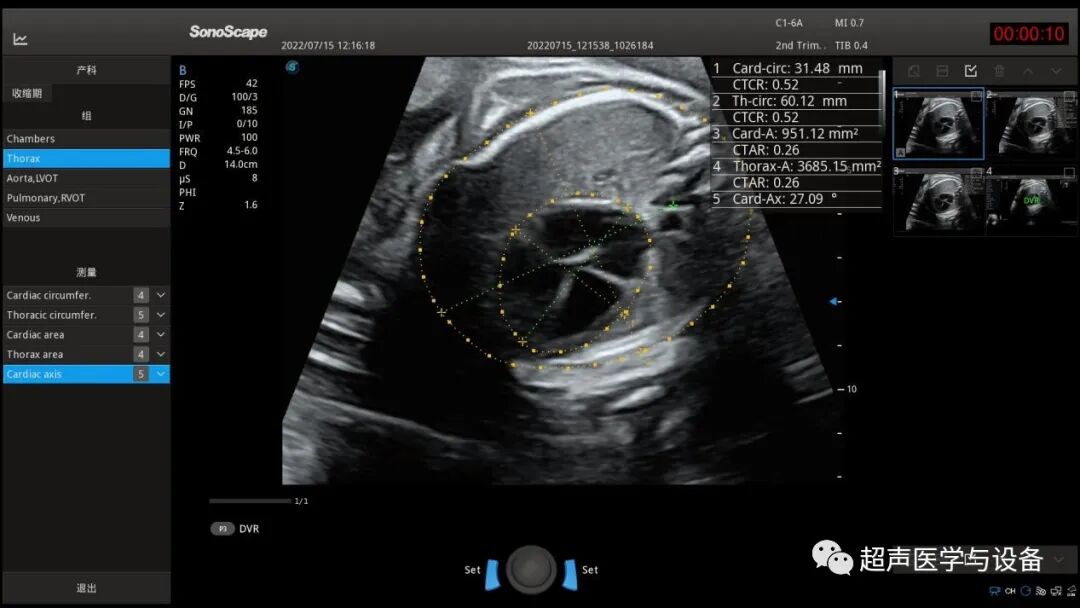

自动测量心胸比例心轴等参数

大大缩短医生手动描迹的时间,可重复性高,数据更加精准。